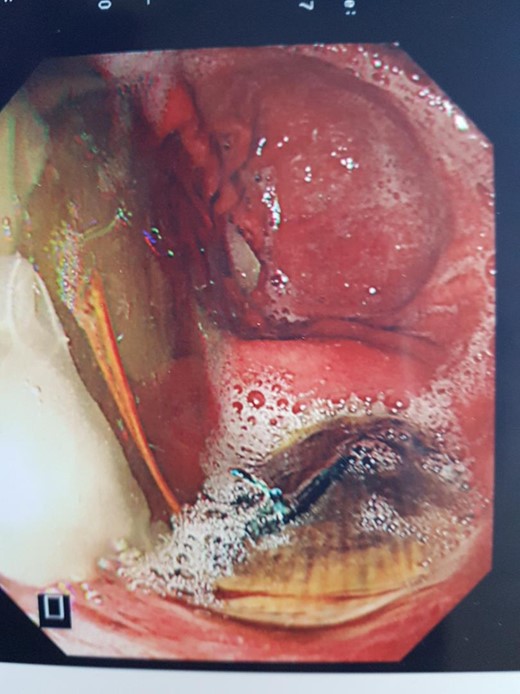

Two months later, repeat OGD revealed a persistent gastric ulcer with a visible segment of aortic stent graft in its base (Fig. 3). He, then accepted the option of definitive repair. He was immediately transferred to a cardio-thoracic tertiary centre where he underwent a thoracotomy, repair of aorto-gastric fistula with primary stomach repair and thoracic and abdominal aorta replacement with a Dacron graft using left heart bypass. He made a good recovery and had no complications. His aortic stent-graft culture grew Candida albicans and vancomycin-sensitive and vancomycin-resistant enterococcus.

Endoscopic view of aortic stent graft in base of gastric ulcer.